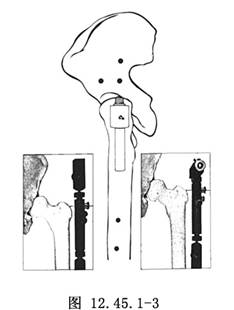

3.將配套模板安裝到導針上,安裝時將模板上的關節軸套入導針。儘管“T”形夾作爲首選,但也可選擇“縱向”形夾(圖12.45.1-3)。